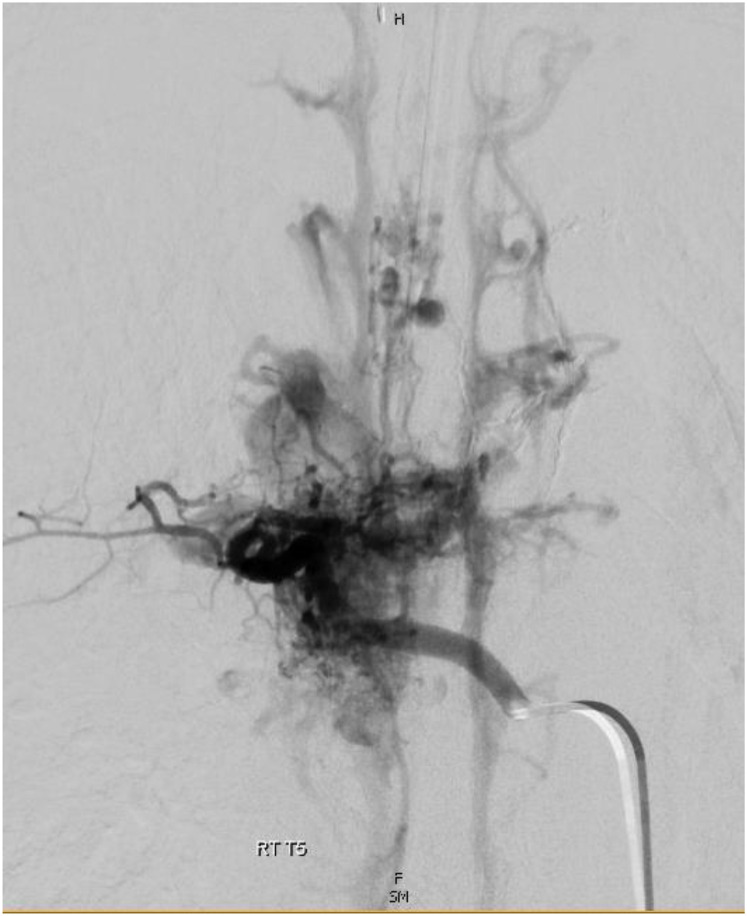

柯布综合征是一种罕见的神经皮肤病,其特征是多发性脊髓血管异常和影响相应皮节的血管性皮肤病变。我们报告了一例 12 岁男孩的病例,他的脊柱动静脉畸形(AVM)延伸至 T4-T5,3 年前部分栓塞后出现胸背部色素沉着斑,并伴有 2 天的背痛、下肢麻木和无力。他的脊柱和脊柱旁组织内有多个 III 型动静脉畸形,涉及 T4 至 T7 椎体,其中以 T4 和 T5 椎体最为广泛。位于主 AVM 瘤巢汇合处的最大动脉瘤是一个 4 毫米的脊髓前动脉瘤,在对主 AVM 瘤巢进行部分栓塞后,动脉瘤完全闭塞。本报告就柯布综合征的自然史、复发风险和治疗方案提供了宝贵的见解,有助于早期诊断和改善预后。

Cobb syndrome is a rare neurocutaneous disease characterized by multiple spinal vascular anomalies and vascular skin lesions affecting the corresponding dermatome. We present a case of a 12-year-old boy with history of spinal arteriovenous malformation (AVM) extending from T4-T5 status post partial embolization 3 years ago and hyperpigmented patch overlying his thoracic back region presenting with 2 days of back pain and lower extremity numbness and weakness. He had multiple Type III AVMs within the spinal and paraspinal tissues involving the T4-T7 vertebral elements, most extensively T4 and T5. The largest aneurysm located at the confluence of the main AVM nidus was a 4 mm anterior spinal artery aneurysm, which was embolized with partial embolization of the main AVM nidus, resulting in complete aneurysm occlusion. This report provides valuable insight on the natural history, recurrence risk, and treatment options of Cobb syndrome to aid in early diagnosis and improve outcomes.